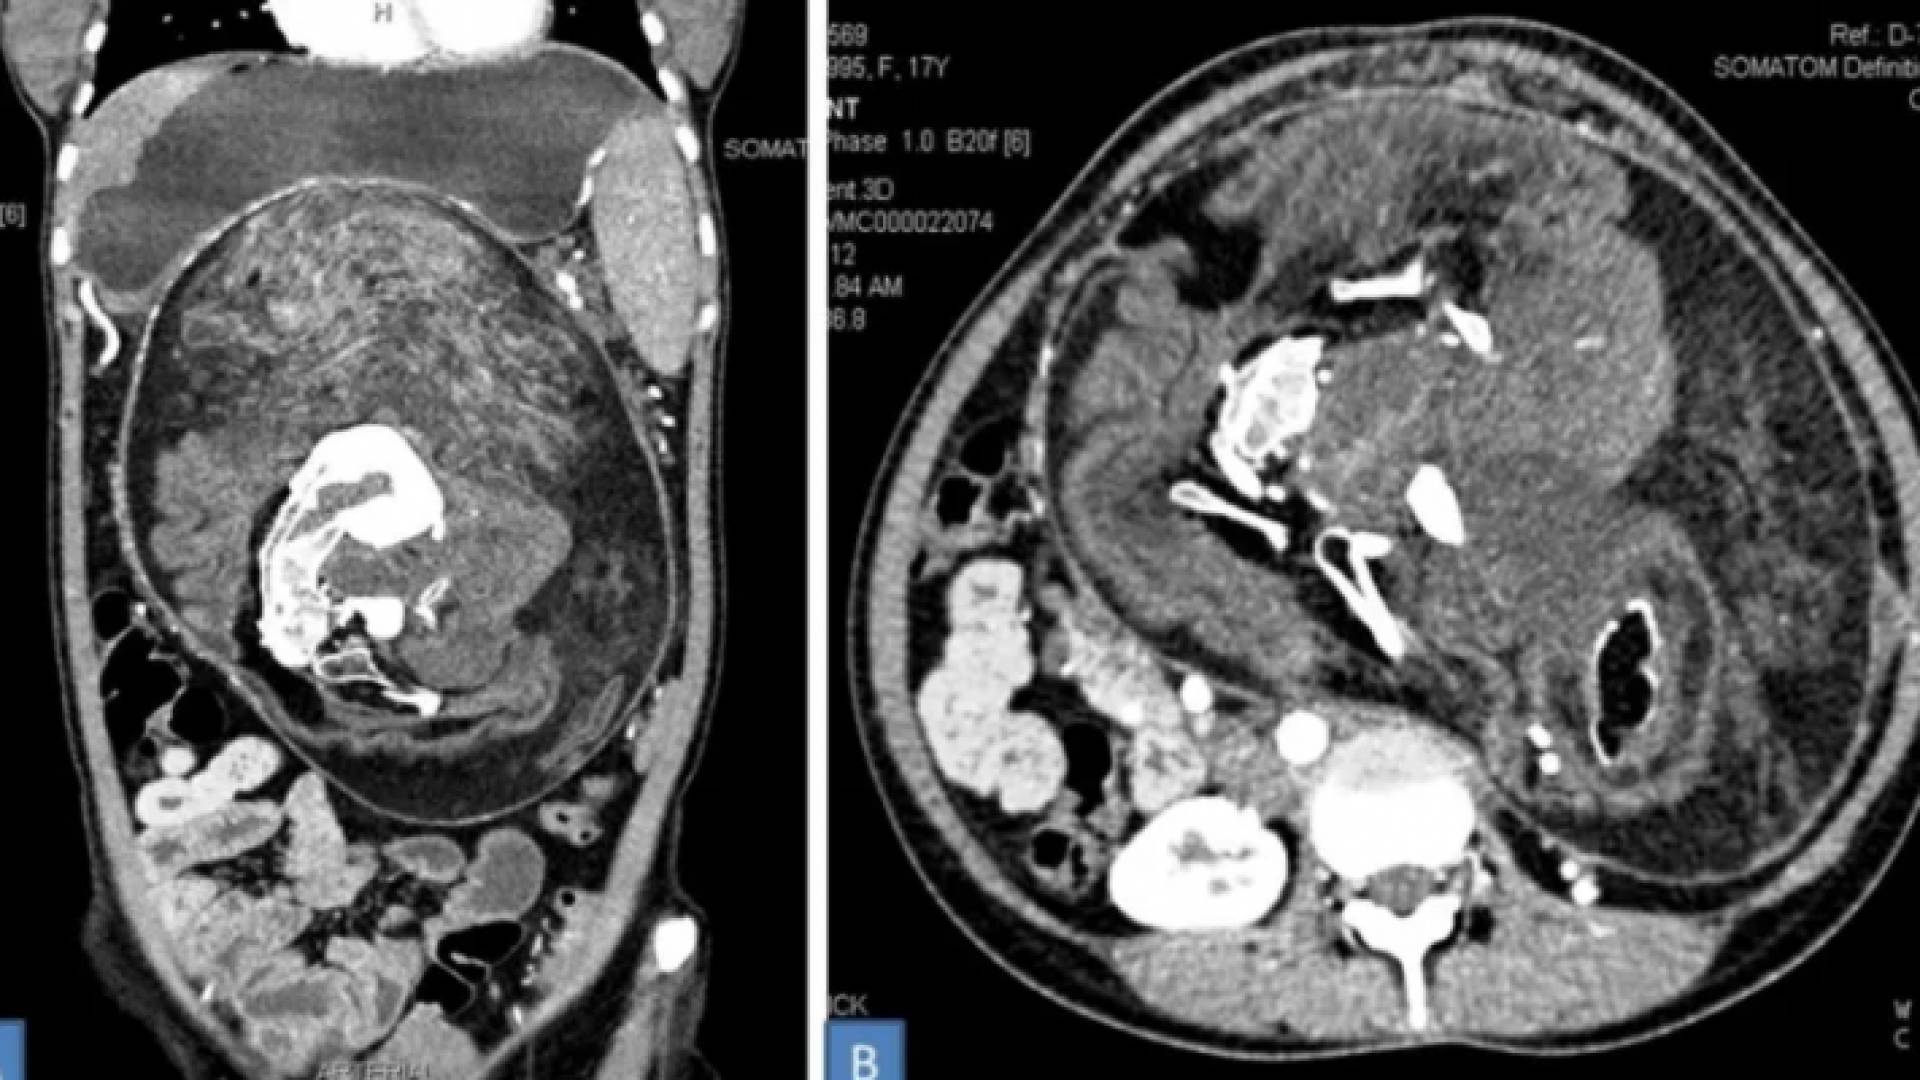

فحص بالأشعة المقطعية للجنين الموجود داخل بطن المرأة

في الفحص البدني الأولي ، كان يشتبه في أن الورم هو ورم. وهو بمعنى ما كان عليه. ولكن عندما قاموا بإجراء فحص CAT على المقطوع ، وجدوا رواسب من الكالسيوم تبدو "على شكل فقرات وضلوع وعظام طويلة" ، وفي النهاية تم اكتشاف الحقيقة الأكثر رعبا. ثم ذهب الأطباء للعمل على إزالته.

ووفقا للتقرير ، فإن محتويات الورم "تتألف من الشعر والعظام الناضجة وأجزاء الجسم الأخرى". وشملت هذه الأجزاء من الجسم "أسنان وهياكل متعددة تشبه براعم الأطراف". كما أن حجمها الهائل - 36 × 16 × 10 سم - سيكون أيضا اجعله الأكبر على الإطلاق في حالة الجنين البالغ في الجنين.